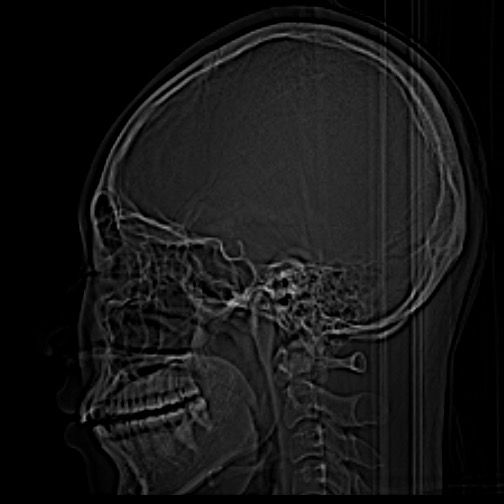

• 1번 째 사진

1. 엑스레이상 큰 문제는 발견되지 않습니다.

2. 단지 소리만 나는 것은 턱관절 질환으로 분류하지 않습니다. 소리가 나는 증상 외에 턱관절 통증, 입 안벌어짐 등의 증상이 동반된다면 구강내과 치과를 가보시기 바랍니다.

3. 모래 갈리는 소리가 난다면 턱관절염의 가능성이 있긴 합니다.